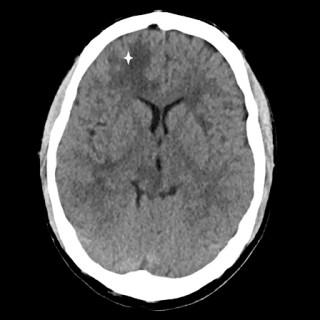

Magesmerter hos barn er en hyppig årsak til henvisning til barnemedisinsk og kirurgisk spesialisthelsetjeneste. Akutt appendisitt, obstipasjon og gastroøsofageal refluks er blant de vanligste diagnosene. Ofte kan barn ha diffuse symptomer, og selv om «det vanligste er det vanligste», er det viktig å være oppmerksom på symptomer som tyder på alvorlig, underliggende patologi. Tett samarbeid mellom fastlege, barnelege, barnekirurg og radiolog kan være viktig for å komme til målet. En jente tidlig i tenårene hadde vært plaget av «treg mage» siden småbarnsalder og hadde gjennom de siste fem årene...